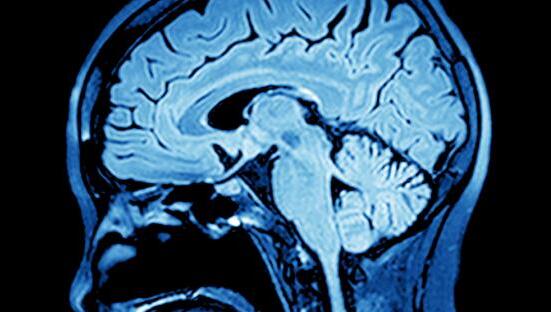

加州大学戴维斯分校和加州大学旧金山分校的研究人员表示,人工智能可以加快对阿尔茨海默氏病关键症状之一的精确检测,他们在《自然通讯》上发表了有关机器学习工具的研究。

研究人员开发的机器学习工具可以检测大脑中称为淀粉样蛋白斑块的蛋白质碎片团块,这些碎片会破坏神经细胞的连接并存在于阿尔茨海默氏病患者中。该工具的工作方式类似于Facebook如何识别所捕获图像上的脸部。它可以很快在脑组织中看到各种淀粉样斑块。